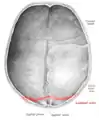

Lambdoid suture seen from above.

The lambdoid suture (or lambdoidal suture) is a dense, fibrous connective tissue joint on the posterior aspect of the skull that connects the parietal bones with the occipital bone. It is continuous with the occipitomastoid suture.

The lambdoid suture is between the paired parietal bones and the occipital bone of the skull. It runs from the asterion on each side.

The lambdoid suture is named due to its uppercase lambda-like shape.